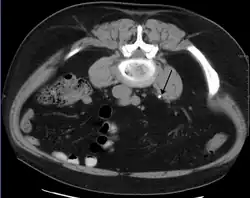

Vaak zijn de klachten samen met het aantonen van bloed in de urine voldoende om de diagnose te stellen. Er zijn echter meer ziekten die zich op een vergelijkbare manier presenteren. Als de klachten en het bloed in de urine in de loop van ongeveer een week niet verdwijnen wordt vaak een echo gemaakt van de nieren om te zien of de steen nog aanwezig is of dat er een andere reden gevonden kan worden voor de klachten. Tegenwoordig wordt er bij nierstenen geen IVP meer gemaakt, een CT-scan van de buik is hiervoor beter geschikt.